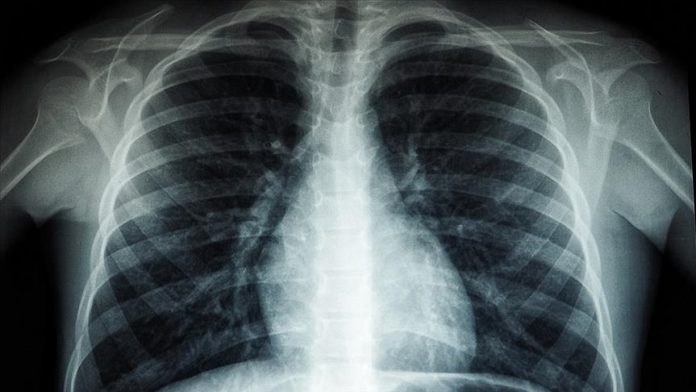

Drejtori Rajonal i Organizatës Botërore të Shëndetësisë (OBSH) për Evropën, Hans Kluge, njoftoi se një milion njerëz vdesin çdo vit nga tuberkulozi, “sëmundja infektive më vdekjeprurëse në botë”.

“Tuberkulozi është sëmundja infektive më vdekjeprurëse në botë, duke vrarë një milion njerëz çdo vit”, tha Kluge.

Ai ka shtuar se rezistenca ndaj ilaçeve, bashkëinfeksioni tuberkuloz-HIV, qasja e pabarabartë në kujdesin shëndetësor dhe financimi i pamjaftueshëm po e përkeqësojnë më tej krizën.

Në “Raportin Global të Tuberkulozit 2025”, të botuar më 12 nëntor, OBSH-ja raportoi se më shumë se 1,2 milionë njerëz kanë humbur jetën nga tuberkulozi në vitin 2024, dhe afërsisht 10,7 milionë njerëz u prekën nga sëmundja